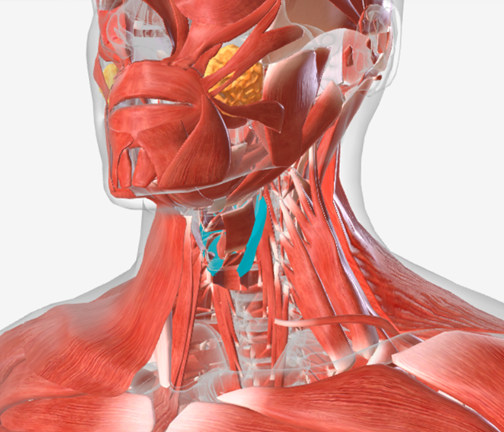

The Resonatory System and The Swallowing System

Anatomy and Physiology of Speech